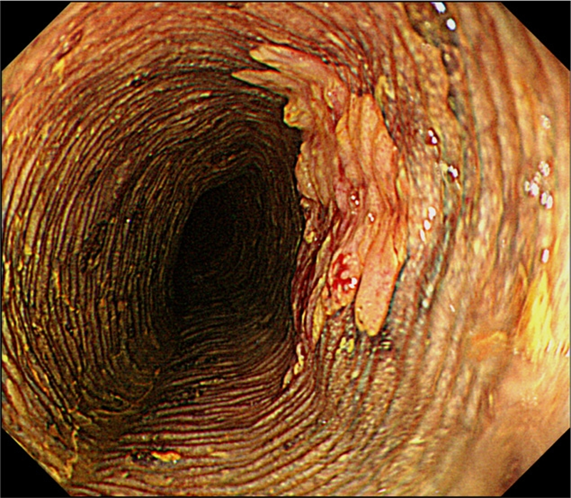

2.“榻榻米”征(见图2)

以传统日本房间用作地板的垫子“榻榻米”命名,指未着色区域规则的褶皱,可能是食管鳞状细胞癌浸润深度的有效指标。

图2  内镜下碘染色显示“榻榻米”征

如果在癌性病变中没有看到“榻榻米”征,肿瘤可能已侵犯到固有层深层;如果看到了“榻榻米”征,则病变侵入深度不超过黏膜肌层。